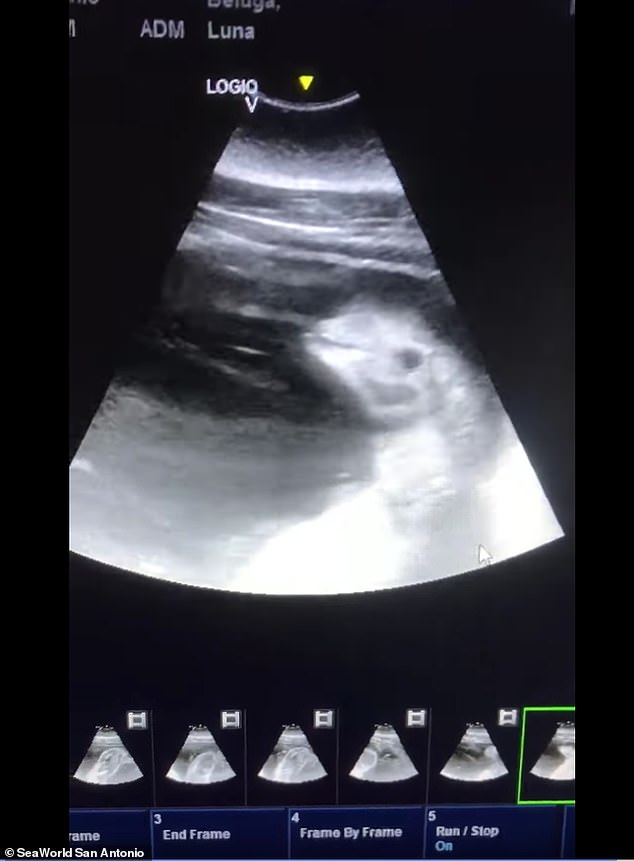

KSAT 등 현지매체 보도에 따르면, 텍사스주(州) 관광명소 ‘시월드 샌안토니오 지점’은 지난 11일(현지시간) 페이스북을 통해 암컷 벨루가 루나(Luna)의 배 속 태아를 촬영한 초음파 영상을 공개했다.

영상은 태아 상태의 새끼 벨루가가 움직일 때마다 그 머리와 눈 그리고 상반신 일부가 나타나는 모습을 담고 있다.

이에 대해 공원 측은 “어미는 ‘허즈번드리 트레이닝’(husbandry training)으로 불리는 특수 훈련을 받은 덕분에 수의팀이 검사하는 동안 가만히 있을 수 있어 초음파 영상을 기록할 수 있었다”고 설명했다. 허즈번드리 트레이닝은 동물원 등에서 멸종 위기에 처한 동물 등을 보존하기 위한 노력의 일부분으로 행하는 훈련 방법을 말한다.